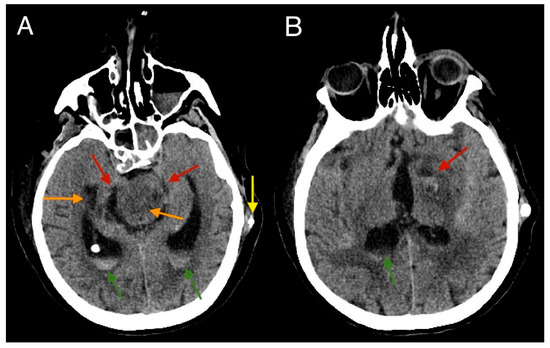

2. Case Report